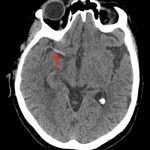

A non-contrast computed tomography (CT) scan showed a hyperdensity along the right middle cerebral artery (MCA) consistent with acute thrombus. The red arrow highlights the hyperdensity in the annotated image.

The dense MCA sign can serve as an important tool in the diagnosis of acute stroke. It typically appears before other signs of infarct are apparent on CT imaging, and identifies an intracranial large artery occlusion and corresponding infarct, in the correct clinical setting.1 Calcifications in the same area of the brain could be mistaken for an MCA sign, but this sign carries a high specificity (95%) and lower sensitivity (52%) for arterial obstruction in ischemic stroke.2 Early identification allows for a wider array of treatment options for a patient with an ischemic stroke, including intra-venous or intra-arterial thrombolysis and mechanical thrombectomy.